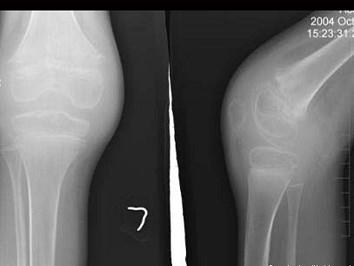

问题 10岁男性患者,左膝关节反复肿胀,活动受限,伴低热2年,经抗炎治疗效果不明显,行左膝关节摄片如图示,最佳诊断是 ( )

选项 A、左膝化脓性关节炎 B、以上都不正确 C、左膝关节结核(骨型) D、左膝关节结核(混合型) E、左膝关节结核(滑膜型)

答案 E